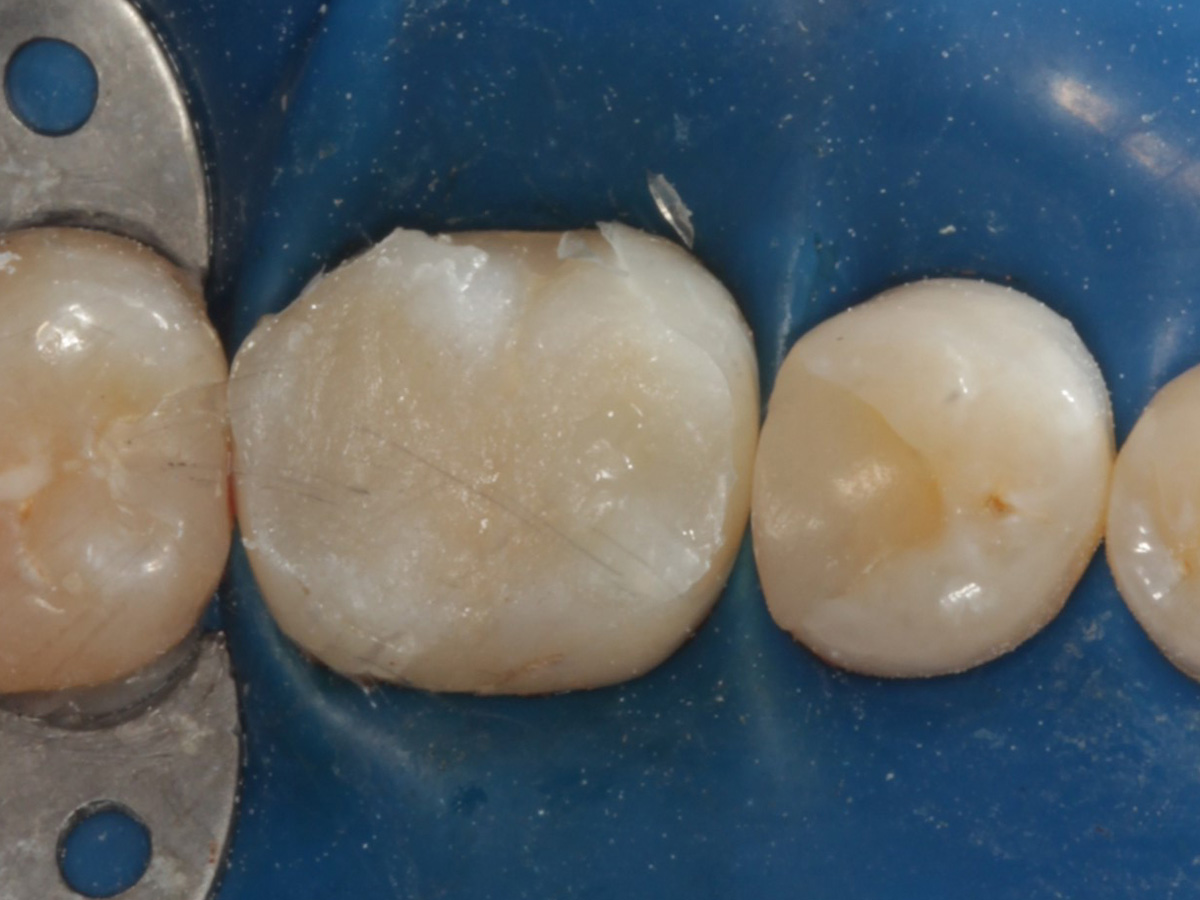

Abbildung 22

Fertige Restauration Zahn 46